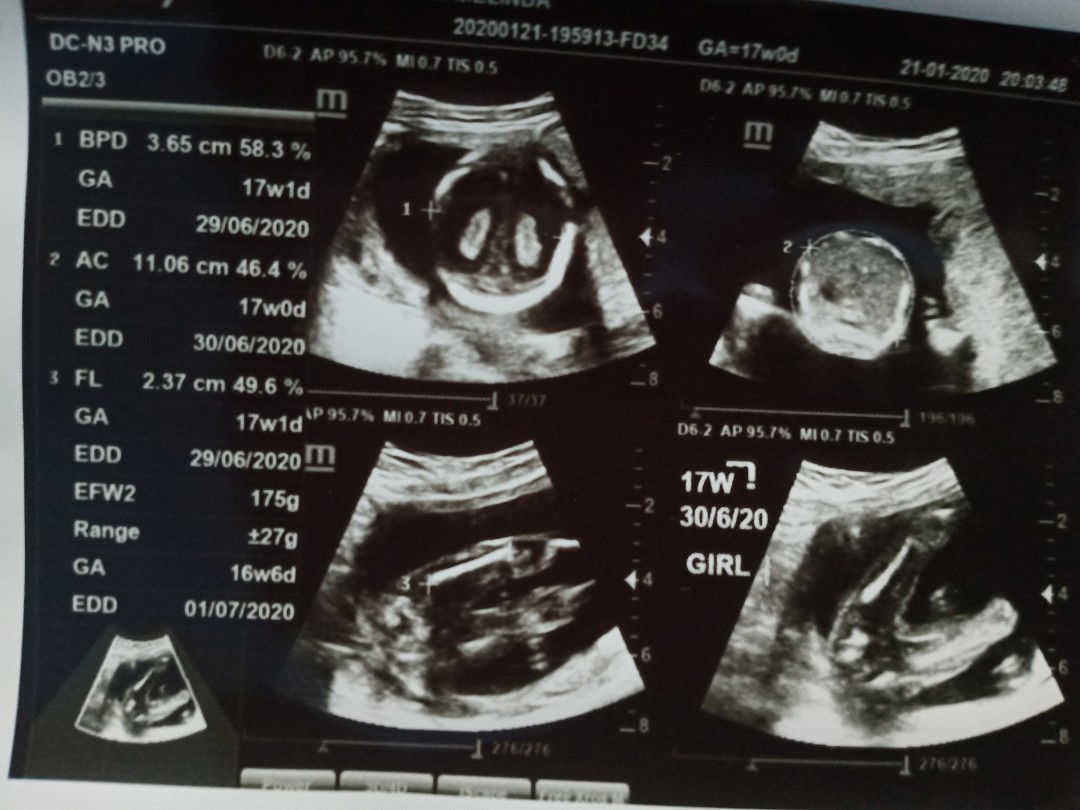

17 week d kasih tau JK

Happy banget bun abis ketemuan sama dede d dalem perut , ini kehamilan k2 ku , dan d kasih baby perempuan.. Sesuai harapanku karna anak pertamaku laki laki.. Semoga sehat terus ya sayang..